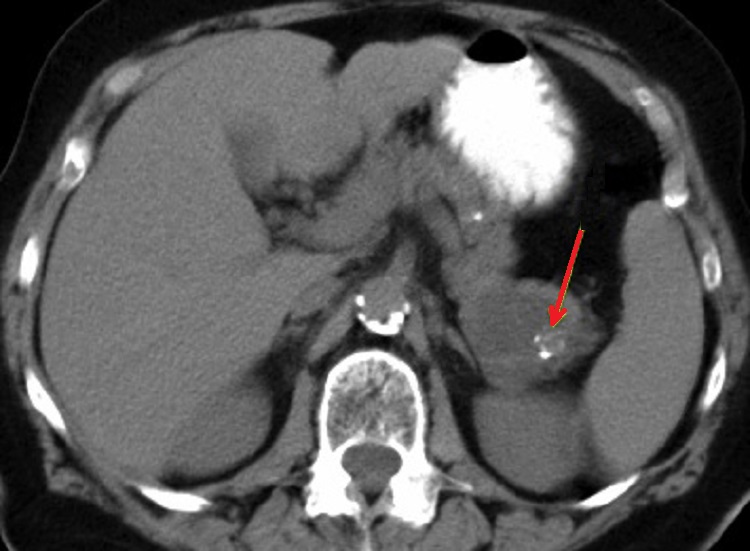

Image radiologique IRM d'une

cystarenome mucineux du pancreas avec aspect

lesionaire de kyste ovalaire uniloculaire a

hyposignal ( fleche rouge ) . Coupe axiale IRM

ponderee T1 |

Meme cas en coupe IRM axiale

ponderation T2 . La tumeur kydtique devient tres

hyperintense ( fleche rouge ) |

|